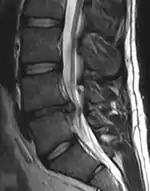

- Magnetic resonance imaging (MRI) without contrast is a diagnostic test that produces three-dimensional images of body structures using powerful magnets and computer technology. It can show the spinal cord, nerve roots, and surrounding areas, as well as enlargement, degeneration, and tumors. It shows soft tissues better than CAT scans. An MRI performed with a high magnetic field strength usually provides the most conclusive evidence for diagnosis of a disc herniation. T2-weighted images allow for clear visualization of protruded disc material in the spinal canal.

A rather severe herniation of the L4–L5 disc

Example of a herniated disc at L5–S1 in the lumbar spine